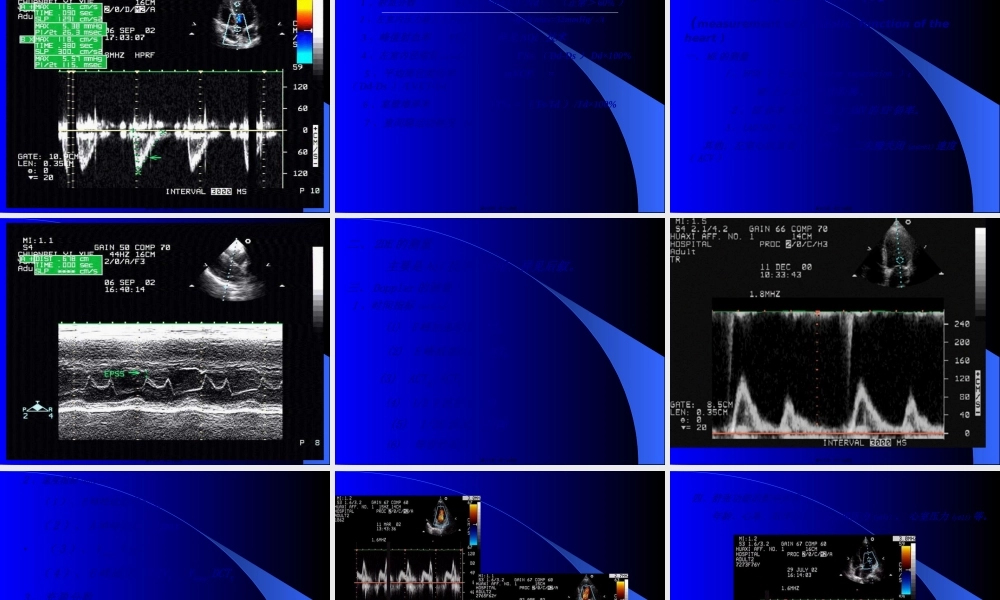

心脏功能(gōngnéng)的超声测量(UltrasonicMeasurementofCardiacFunction)曹礼庭第一页,共二十四页。心脏收缩功能的测定(measurementofsystolicfunctionoftheheart)流量指标内容时间(shíjiān)指标速度指标泵功能指标第二页,共二十四页。基本检查指标EDV(左室舒张期末容积,ml)ESV(左室收缩期末容积,ml)SV(每搏量)SV=EDV-ESV正常值60~130mlCO(心输出量)CO=SV×HR正常值3-6L/minCI(心脏指数(zhǐshù))CI=CO/BSA正常值2-3L/min/m2EF(射血分数)EF=SV/EDV正常值60~75%第三页,共二十四页。一、流量指标1、ME容量(róngliàng)计算法椭圆形体积法V=π/6.LD2=π/62DD2=1.047D3立方体积法V=1.047D3=D3Teichholtz校正公式V=7.0×D3/(2.4+D)据此可以计算出其它指标。第四页,共二十四页。第五页,共二十四页。2、2DE容量计算法(1)、单平面法面积长度法:取心尖二腔或四腔观,测出左室的面积A及长径L.根据:V=8A22/3πL=0.85A22/L/L单平面Simpson’s法:V=∑Ah⊿注:美国(měiɡuó)超声心动图协会推荐,应用改良Simpson’s公式,将两个长轴分为20个等份,将平面相加,计算LV容积.可推算其它指标.第六页,共二十四页。舒末左心室容积(róngjī)收末左心室容积(róngjī)第七页,共二十四页。陈旧(chénjiù)心梗,心尖部室壁瘤Simpson法测量左室容积第八页,共二十四页。(2)双平面法:取二尖瓣水平短轴观及心尖二腔或四腔观,测出二尖瓣水平短轴面积(miànjī)Am及左室长径L.根据:圆柱-圆锥体法:V=2Am.L/3圆柱体法:V=Am.L圆柱-半椭圆体法:V=5Am.L/6(3)三平面法(改良Simpson’s法/圆柱-截头圆锥-圆锥体法)V=Am.L/3+(Am+Ap)/2×L/3+1/3Ap.L/3Ap:乳头肌短轴左室的面积。第九页,共二十四页。3、Doppler计算(jìsuàn)法主动脉血流计算法SV=A•VTIA:Ao根部面积A=π/4D(ME/2DE测量)。VTI:AVO速度时间积分。二尖瓣血流计算法SV=A•VTIA:MVO面积。VTI:MVO舒张期速度时间积分。据此可推算:每分量CO=SV•HR(HR心率)每搏量CI=CO/BSA(BSA体表面积)第十页,共二十四页。第十一页,共二十四页。二、时间指标1、射血前期(qiánqī)(PEP):ECG的Q波----PDE上AV开放的时间。2、射血时间(LVET)ME上AV开放点----关闭点的时间。PDE上AV开放信号-----关闭信号的时间。3、PEP/LVET4、等容收缩时间ICTECG的R波-PDE上AV开放的时间减去ECG的R波-PDE上MV关闭的时间。5、总电机械收缩时间(TEMS)ECG的Q波----AV关闭点的时间。第十二...

3、如文档内容存在违规,或者侵犯商业秘密、侵犯著作权等,请点击“违规举报”。

碎片内容